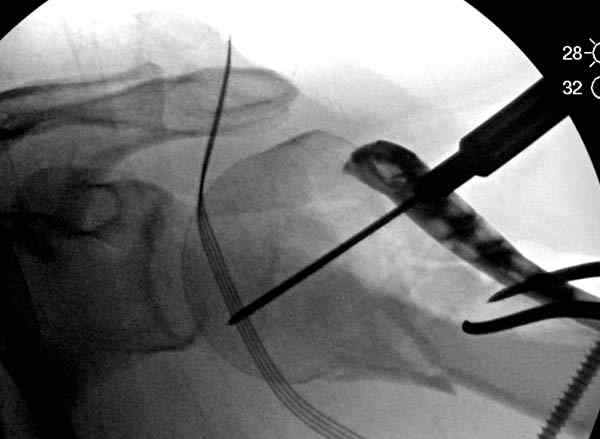

Здесь пример открытой репозиции 57 летнего с переломом плеча (1,2)  смещение обнаружено на  интероперационном снимке. При нормальной прямой проекция (3) угловое смещение обнаружили в аксиальной проекции (4)

После устранения смещения пластина установлена выше (5,6,7) и финальные снимки (8,9,10)